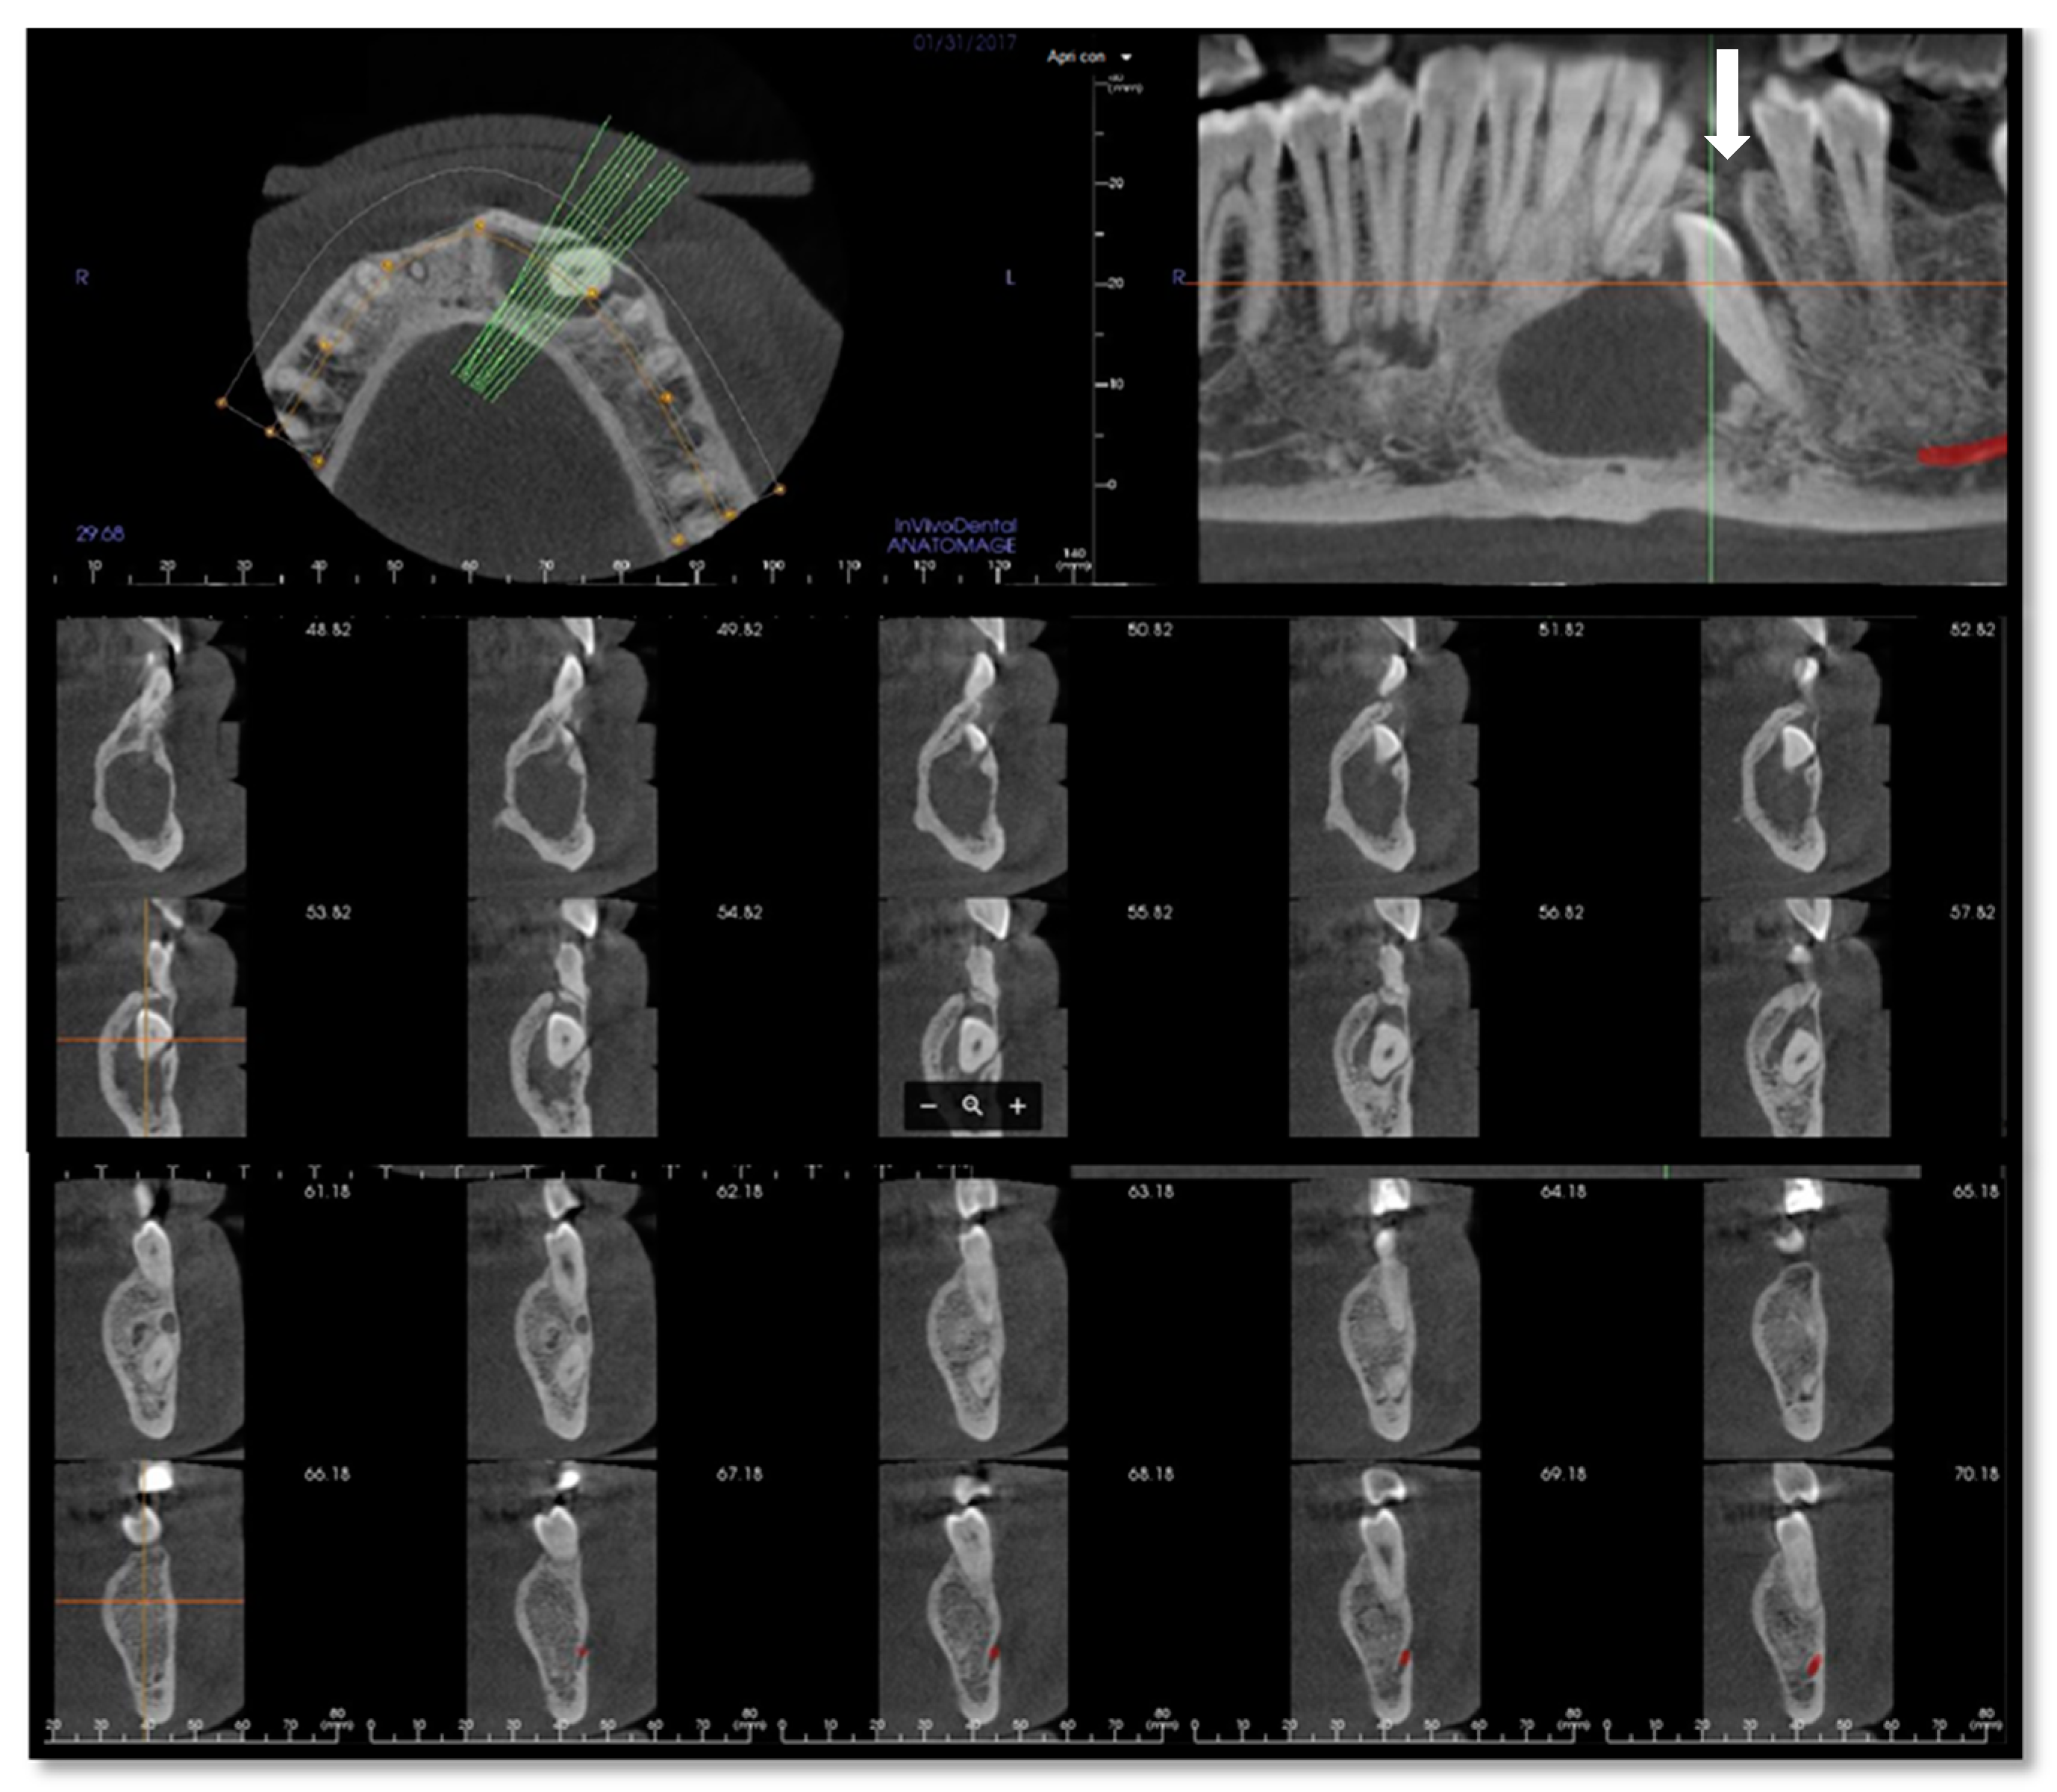

Virtual surgical planning software ProPlan CMF (Depuy Synthes, Solothurn, Switzerland, and Materialise, Leuven, Belgium) was used for detailed planning of reconstruction with vascularized fibular flap. Planning began with conversion into three-dimensional (3D) virtual models of maxillofacial and lower extremities CT data (Figure 7). The surgeon determined virtually the resection margins and localization of the optimal angles for mandibular osteotomies, used for producing the osteotomy guides. Fibula osteotomy guides were also prepared, following virtual mandibular reconstruction and automatic adjustment of the fibula segments length and osteotomy angles (Figure 8).

Figure 7.

ProPlan CMF (Depuy Synthes, Solothurn, Switzerland, and Materialise, Leuven, Belgium) preoperative surgical planning of mandibular resection vascularized fibular flap reconstruction. (a) Mandibular defect; (b) mandibular reconstruction planning, coronal view; (c) mandibular reconstruction planning, axial view; (d) fibular segmentation planning.

Figure 8.

Osteotomy cutting guides.